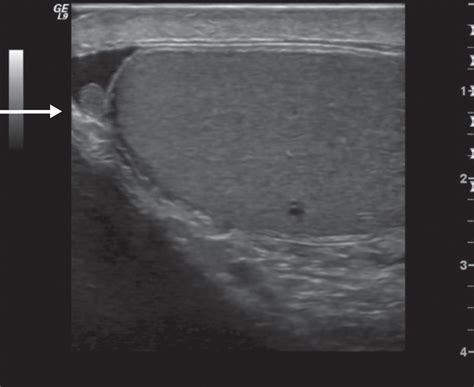

Color Doppler Ultrasound is particularly vital. It allows the radiologist to visualize the blood flow within the affected testicle. If the testicle itself shows normal blood flow but a small, hypoechoic or hyperechoic area is visible at the upper pole, it strongly supports the diagnosis of a torted appendix testis rather than testicular torsion.